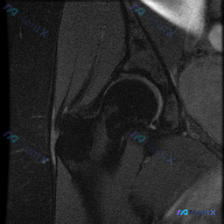

整理了一例很有启发的髋关节MRI读片病例,分享一下我的分析思路,大家也可以一起讨论。 病例影像基础信息 这是一张髋关节冠状位T1加权MRI,我们先梳理所有可见的异常: 1. 股骨头区域:股骨头轮廓完整,关节间隙尚存,没有明显严重塌陷;但在股骨头前上方承重区,可见清晰的线样/带状低信号影,边界清楚,符...